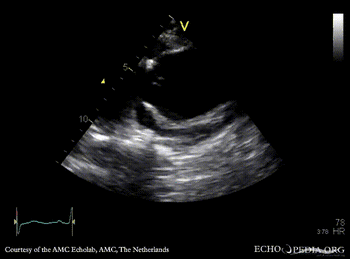

Dilated ascending aorta, severe aortic regurgitation

PLAX: dilated left ventricle and ascending aorta in patient with Marfan syndrome PLAX: dilated ascending aorta